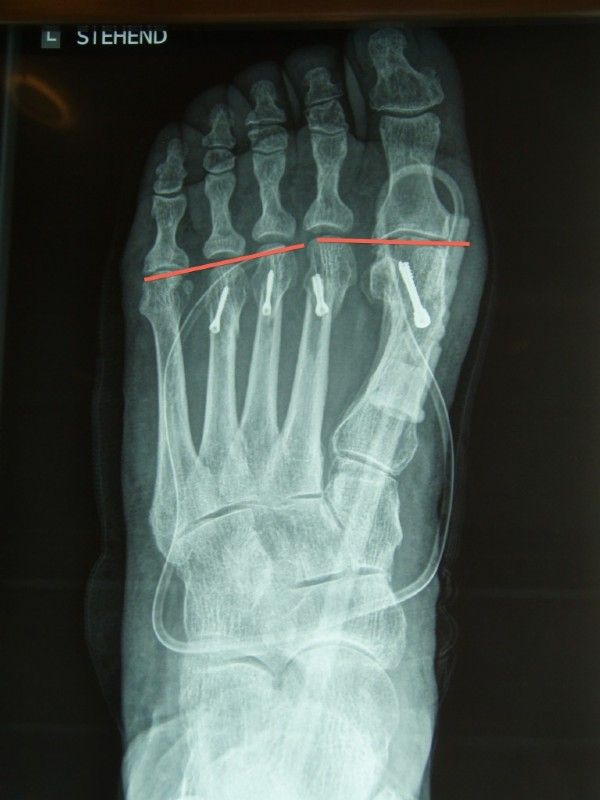

Spreizfuß Röntgenaufnahme

After an elsewhere conducted, improper hallux surgery with shortening of the metatarsal I, the II, III. and IV bone became relatively lengthier, shown here by the yellow lines.

The patient suffered from massive splay problems that were not controllable with conservative measures. Therefore, a further operation had to be carried out. The red lines show the planned shortening in the re-operation.

Both feet had to undergo a shortening of the metatarsals. The parable was achieved and the splayfoot problems disappeared after a short time.